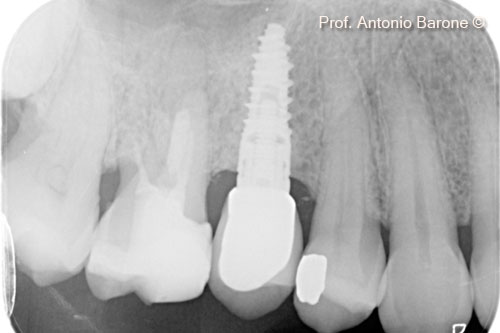

Chụp X-Quang quanh chóp răng kèm đặt implant

Hình ảnh X-Quang chóp răng 1 năm sau khi cấy ghép implant

Hình ảnh X-Quang chóp răng 3 năm sau khi cấy ghép implant

Hình ảnh X-Quang chóp răng 7 năm sau khi cấy ghép implant